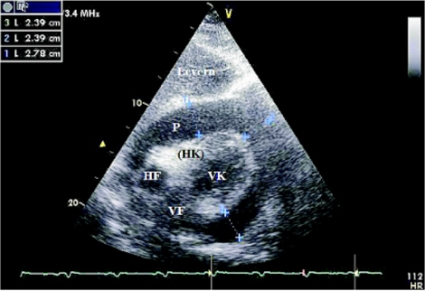

Med ekokardiografi kan hjärtstorlek och såväl höger- som vänsterkammarens systoliska funktion bedömas. Med dopplerteknik kan vänsterkammarens diastoliska funktion undersökas och fyllnadstrycket uppskattas. Om det finns perikardvätska måste fyllnaden till höger kammare undersökas för att bedöma om hjärttamponad föreligger. Vid klaffläckage eller förträngningar ger dopplerundersökning snabb diagnos. Vid lungemboli kan påverkan på högerkammarfunktionen ibland ses, och den är direkt relaterad till prognosen [16, 22].